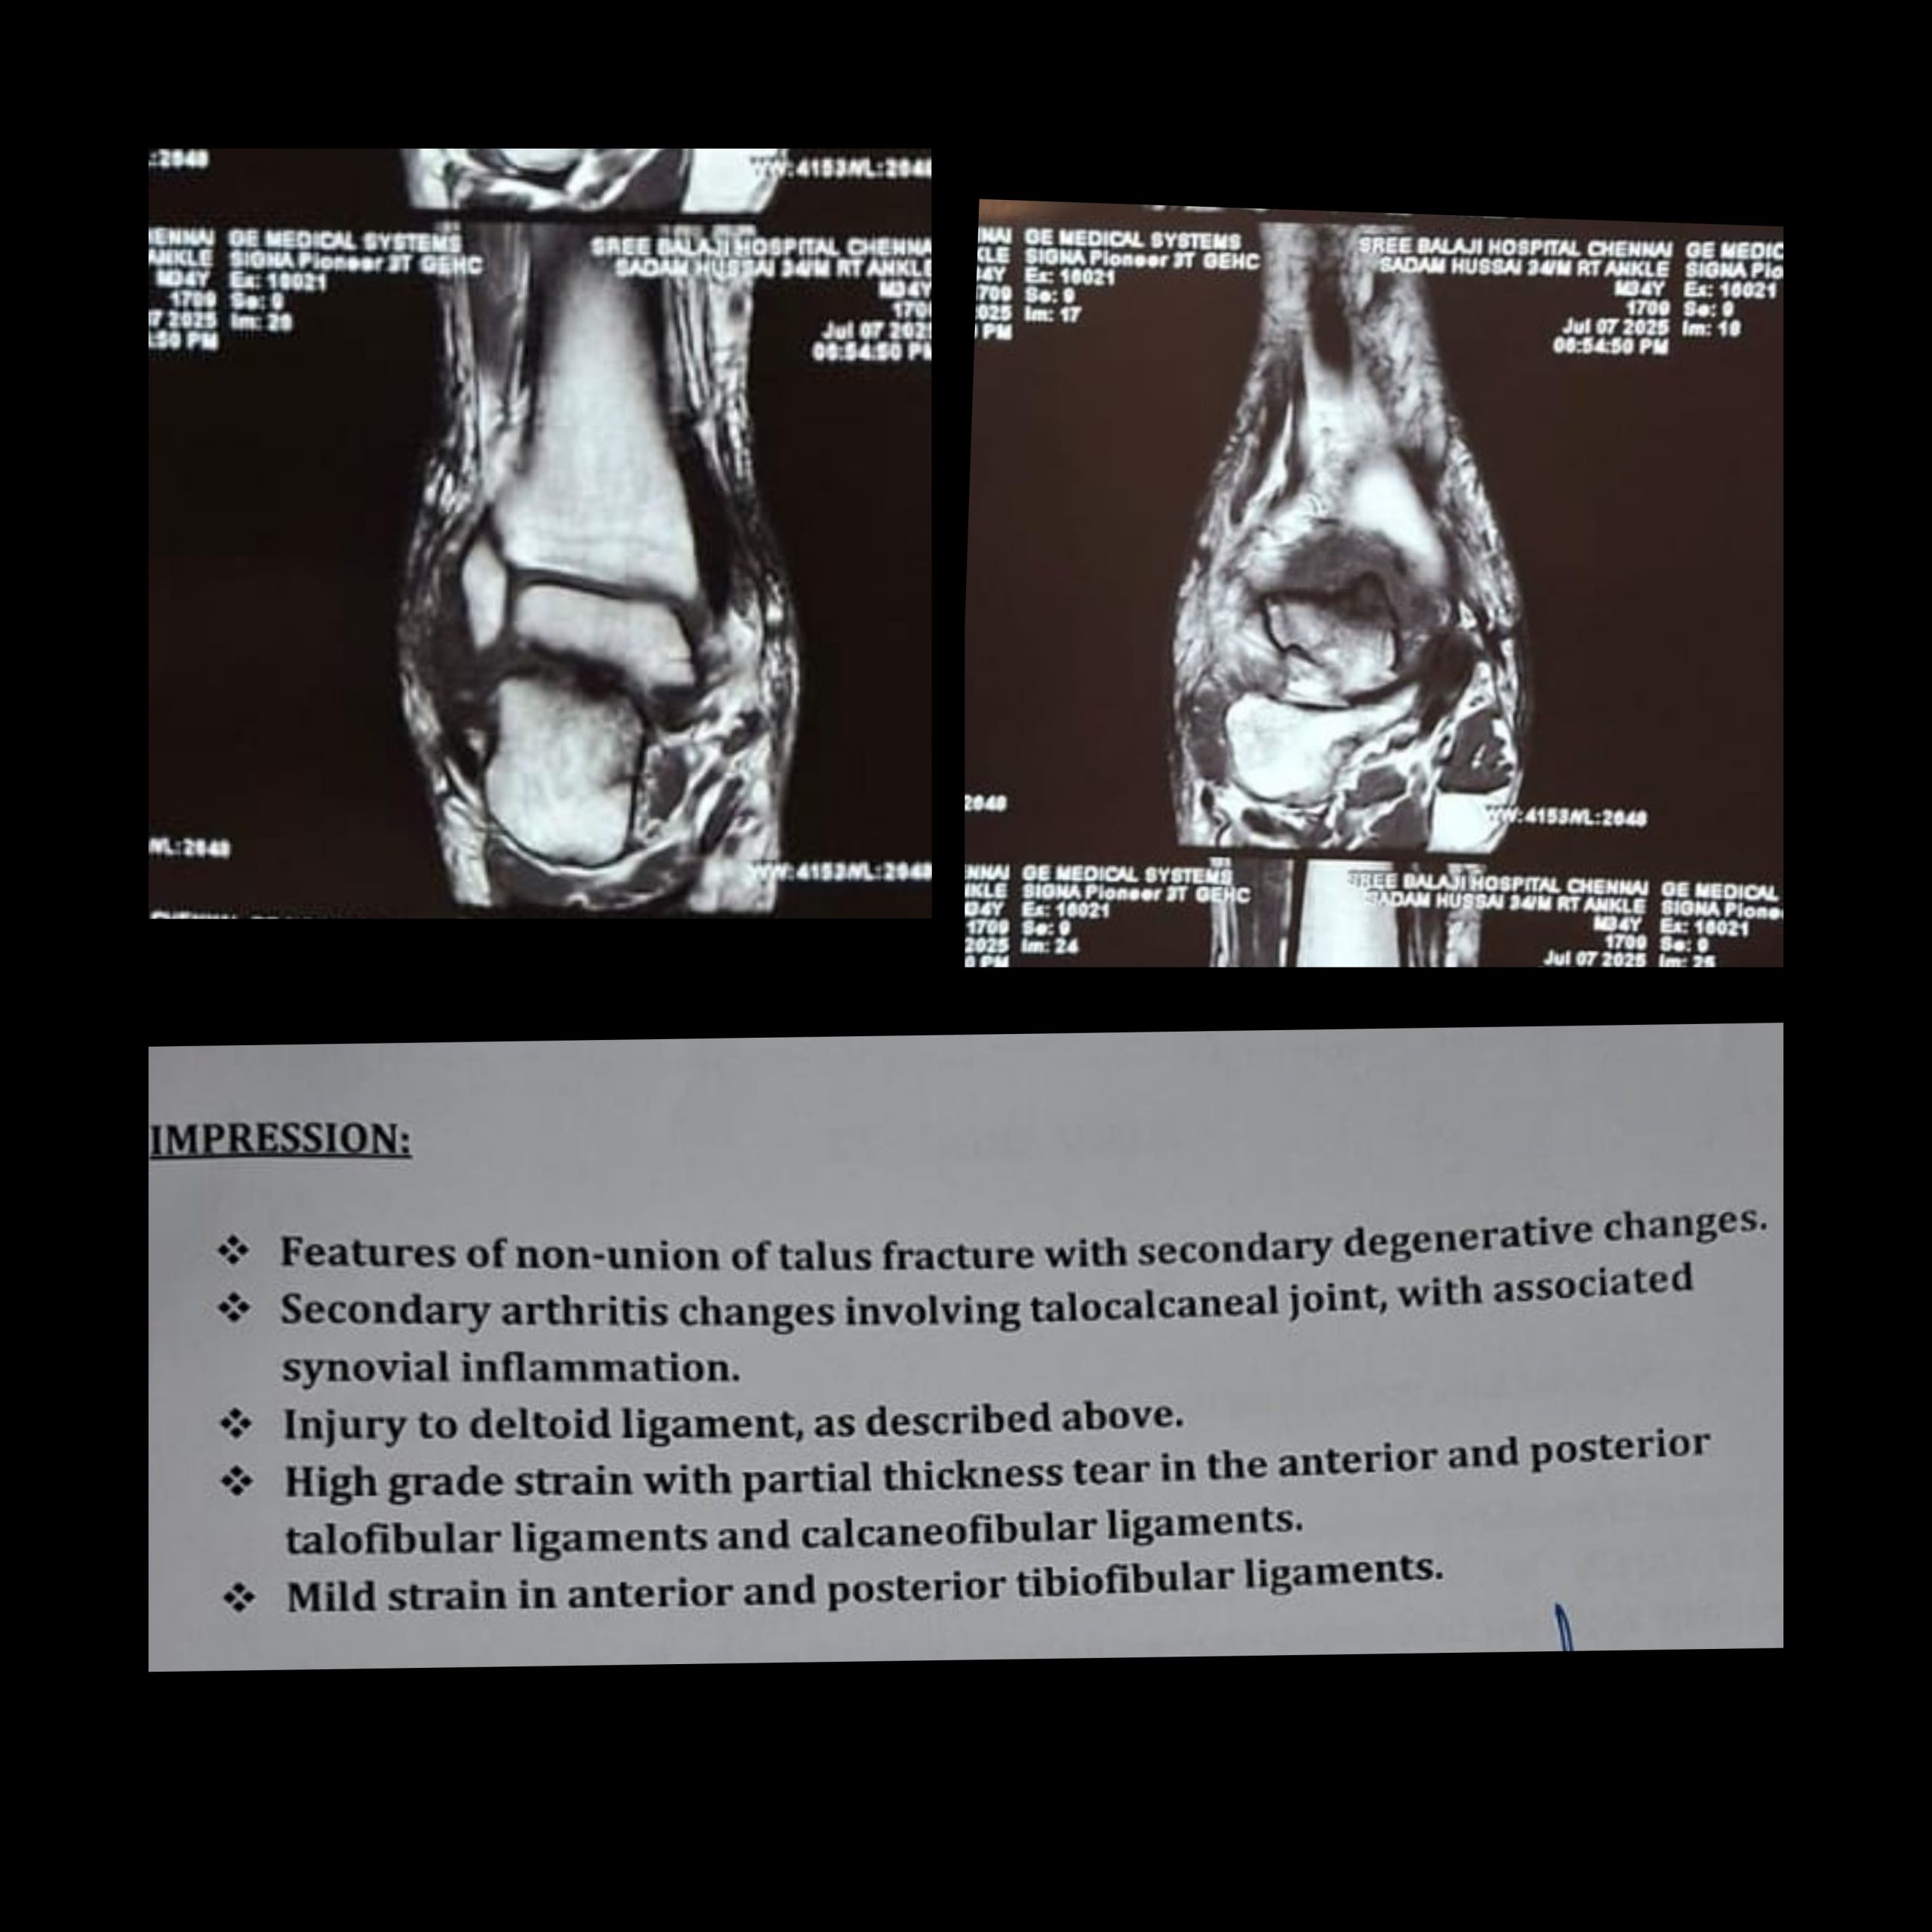

A computed tomography scan confirmed a non-union of the talar body fracture with sclerosed fracture margins and minimal displacement. Features of non-union of talus fracture with secondary degenerative changes with Secondary arthritis changes involving the talocalcaneal joint (Fig. 2).

Figure 2: Pre-operative computed tomography scan.

Magnetic resonance imaging was suggestive of features of non-union of talus fracture with secondary degenerative changes. Secondary arthritis changes involving the talocalcaneal joint, with associated synovial inflammation. Injury to the deltoid ligament with high-grade strain with partial thickness tear in the anterior and posterior talofibular ligaments and calcaneofibular ligaments (Fig. 3).

Figure 3: Pre-operative magnetic resonance imaging.